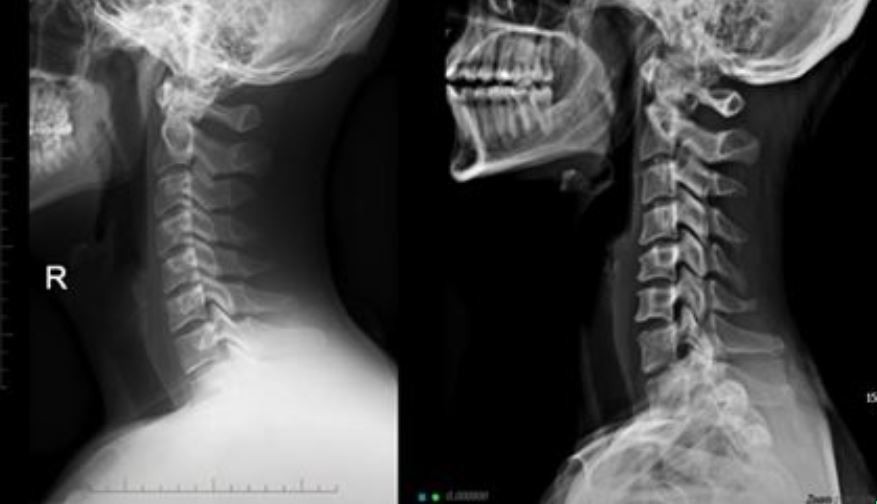

오늘은 목 건강을 위협하는 질환, **목디스크(경추 추간판 탈출증)**의 증상에 대해 이야기하려 합니다. 목디스크는 목뼈 사이에 있는 디스크가 제자리를 벗어나 신경을 압박하면서 발생하는 질환입니다.

목디스크는 목 통증뿐만 아니라, 신경 압박으로 인해 신체의 다른 부위에도 다양한 증상을 유발합니다. 다음은 목디스크 환자들이 흔히 겪는 10가지 주요 증상입니다.